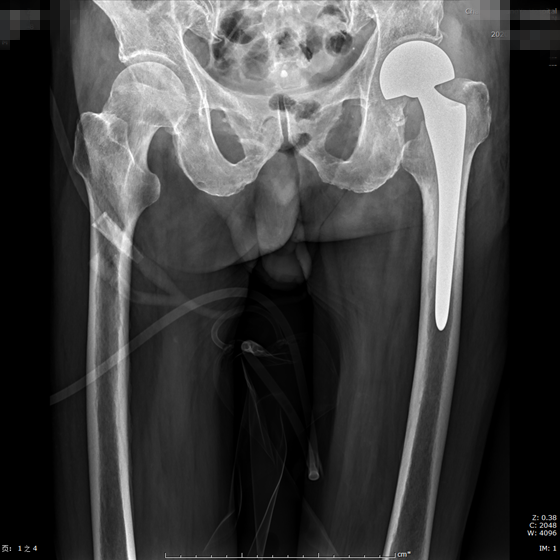

术后

“做完手术,可能几天后就可以下地活动了,这个也要看老人的身体情况。入院后,骨科主任张朝跃教授、周天宝副主任医师和邹敏副主任医师为李爷爷制定了完善的术前计划和手术方案。4月1日,李爷爷进行了“左侧人工股骨头置换术”,手术十分顺利。术后老人明显感觉左下肢疼痛减轻,术后第1天就能下床活动。经过医护人员的精心护理,李爷爷现已康复出院。